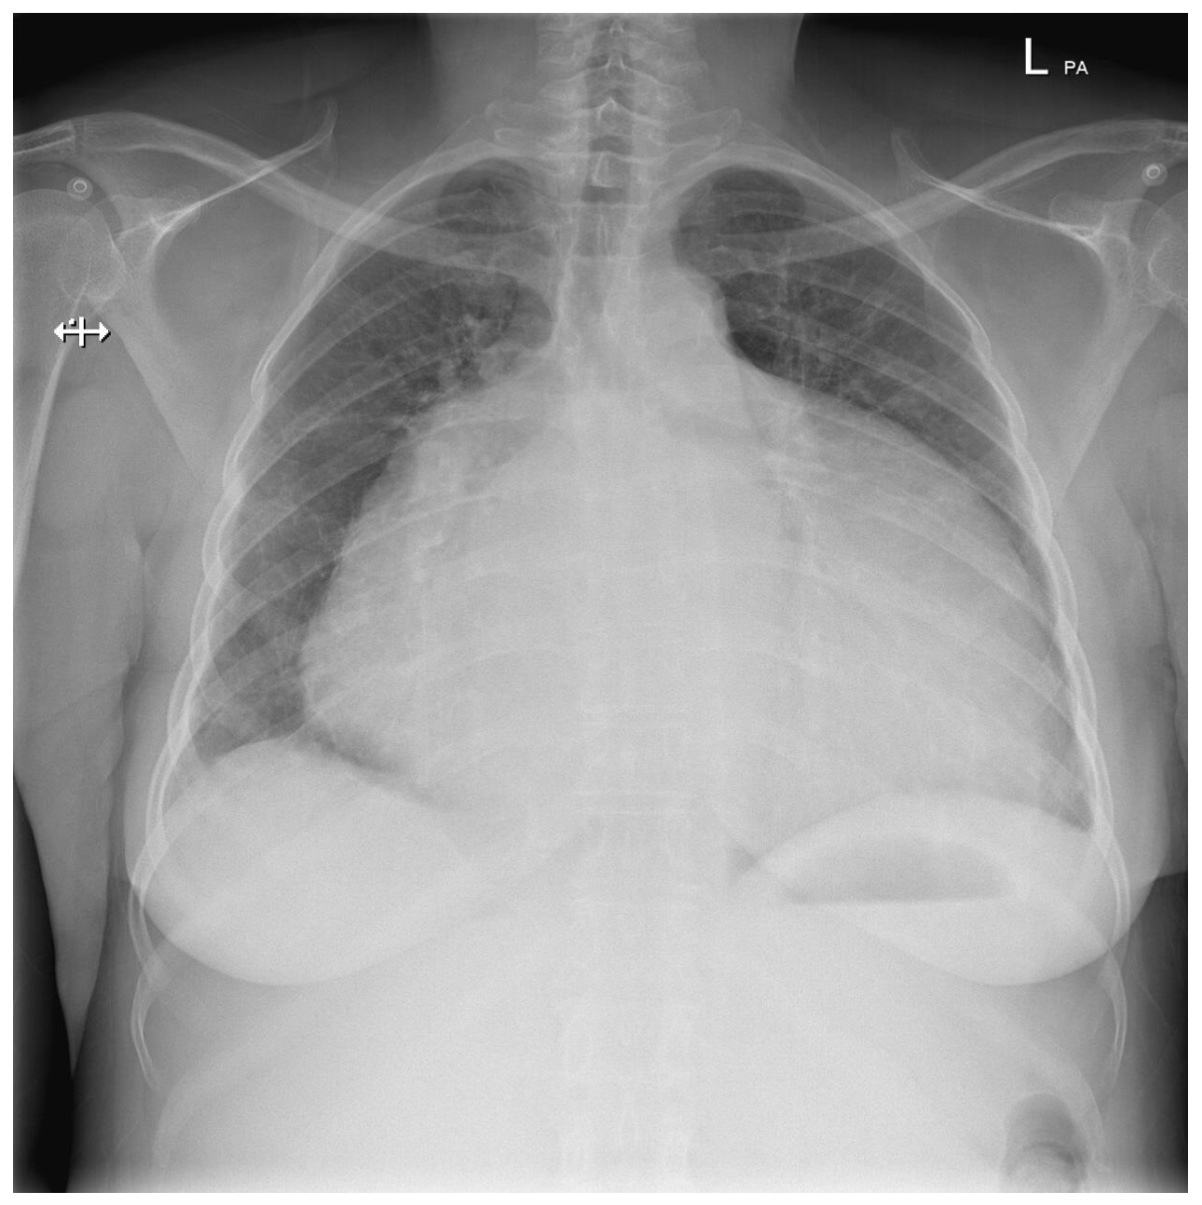

Cardiomegaly

Heart failure

Alveolar oedema

Cardiomegaly (although AP so can’t assess properly)

Dilated upper lobe vessels

Pleuarl effusion